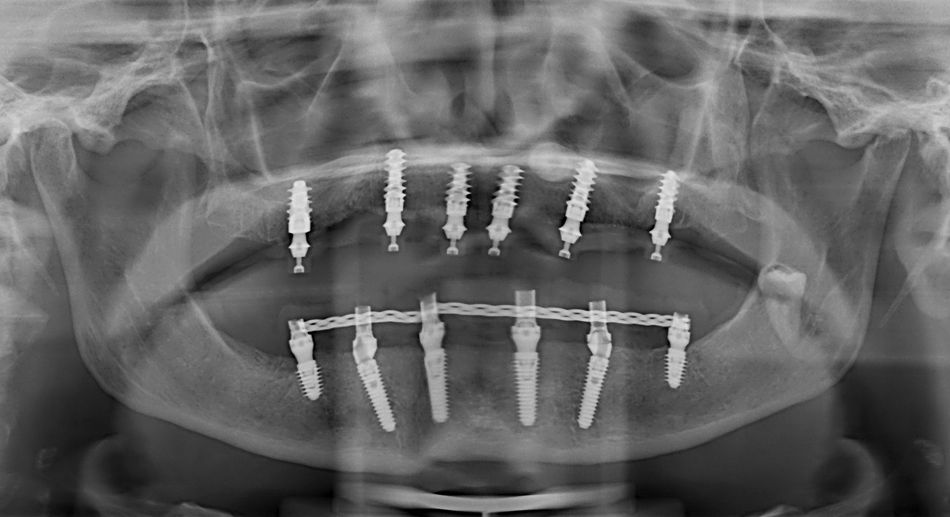

Later, we rehabilitated the mandibular arch with a Toronto prosthesis located on six implants (Fig. 3).

Since her oral hygiene was permanently improved, we decided to reward her by delivering a fixed prosthetic solution immediately loaded on six BLX implants.

We placed Straumann® Roxolid® SLActive® 4.5mm-diameter implants in the sites 13, 11, 21, 24 and 26, and a 5.5mm-diameter implant in 16. All the fixtures were 10mm long except for 13 and 24, which were 12mm long (Figs. 5,6,8).